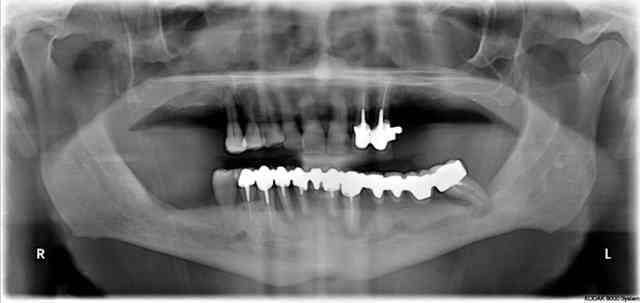

regardes cette radio panoramique par exemple...

petit indice, le "bientôt mci", à ton avis, il reste quoi actuellement (j'ai fait du "ménage")

Bientot mci f87uuw - Eugenol